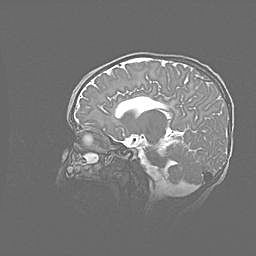

Неполная лизэнцефалия (пахигирия). Открытая гидроцефалия.

Возраст: 17 дней

Вес: 3110 г

Пол: мужской

Окружность головы: 33,5 см

Срок гестации: 35-36 недель

Лизэнцефалия—недоразвитие корковой пластинки и мозговых извилин в результате нарушения миграции нейронов коры. Поверхность мозговых полушарий гладкая. Микроскопически выявляется отсутствие нормальных слоев коры и скопление групп нейронов в подкорковом белом веществе.

Пахигирия—уменьшение числа вторичных извилин. В пораженном полушарии нервные клетки образуют толстый недифференцированный слой с неправильно расположенными нервными волокнами и группами гетеротопных клеток. Нервные клетки незрелые. Белое вещество истончено. При этом нередко аномально развит корково-спинномозговой путь.